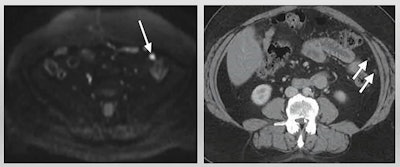

Sahdev cited previous research touting MRI over CT. The most recent research was a 92-patient study published in 2020 in the European Journal of Radiology, which showed that diffusion-weighted imaging (DWI) MR had overall higher accuracy than CT in evaluating all sites. DWI also performed "significantly better" than CT for involvement of mesentery, periaortic lymph nodes, and bowel serosa.

Another study Sahdev cited was published in 2016 in the British Journal of Radiology. The authors found that diffusion-weighted MRI had higher overall sensitivity than CT, 98% to 83%. They also found that MRI detected more surgically critical sites, such as smooth muscle actin activity, small- and large-bowel serosa, and mesenteric root, among others. However, the researchers did not validate their disease sites with histology or surgical findings, Sahdev said.

Still, Sahdev said MRI has advantages via increased tissue contrast and increased conspicuity for small lesions through diffusion-weighted MR. It also shows direct disease response with alterations in apparent diffusion coefficient measurements.